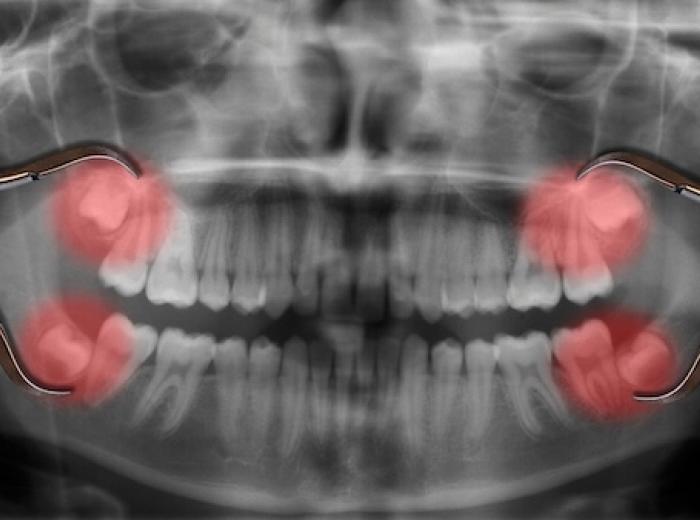

Impacted Wisdom Teeth